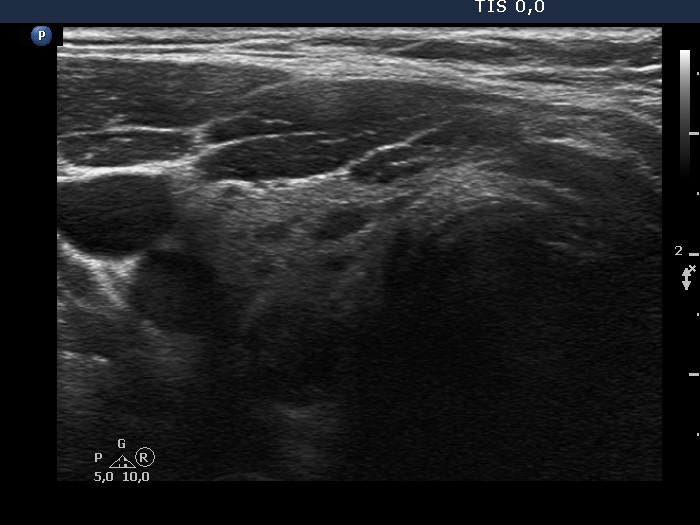

First examination (1st row of images)

Clinical presentation. A 45-year-old man was referred for cytology of a discrete lesion found on ultrasound examination. The patient had been treated for hypothyroidism for several years.

Palpation: no abnormality.

Hormonal evaluation: TSH 2.19 mIU/L on daily100 microgram levothyroxine.

Ultrasonography. The thyroid presented the typical focal form of lymphocytic thyroiditis, it had numerous, tiny, hypoechoic areas. There was a more regularly shaped and larger lesion in the dorsal part of the right lobe. This lesion had at least one punctate echogenic focus.

Aspiration cytology of the lesion resulted in Hashimoto's thyroiditis.